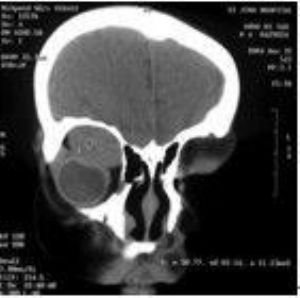

3. CT扫描 肿瘤多位于眶上部,形状不规则,或呈锥形、类圆形(图)等,边界清晰或不清晰,密度均一,肿瘤内如有出血,则密度不均。

冠状位CT显示右眶上部横纹肌肉瘤,肿瘤呈椭圆形,边界清晰,均质,眼球受压变性,骨质无破坏。(请见下图)